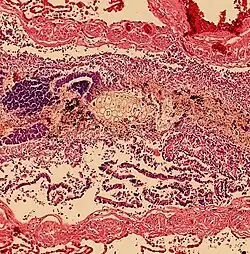

Aspiration pneumonia

Aspiration pneumonia is when bacteria is carried into the respiratory tract via aspiration and subsequently causes an infection of the lung. Any substance or object that is aspirated into the airway has the potential of carrying infectious agents with it into the respiratory tract. It primarily affects older adults and can be especially severe in patients with learning disabilities, or disorders of abnormal swallowing.[14]

Aspiration pneumonitis

Aspiration pneumonitis (Mendelson's syndrome) is chemical injury of lung tissue secondary to aspiration of regurgitated gastric acid.[15] The syndrome was first described among pregnant patients[16] after the administration of anesthesia, though it can occur in any scenario where gastric contents are aspirated.[17]